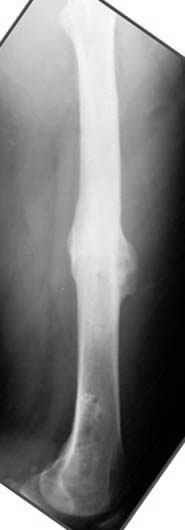

На рисунке N1 предоперационный план лечения ложного сустава шейки бедра- линия ложного сустава, угол и направление введения импланта, клиновидная остеотомия в градусах и миллиметрах, второй снимок после коррекции, расчет, на сколько удлиняется конечность и размеры импланта;

N3 рисунок окончательный снимок, после операции моя рентгенограмма должен выглядеть примерно как эта картина. На N4 снимке клин перед удалением; N5 послеоперации 3 нед.; N6 окончательная рентгенограмма.

пластическая модель; и коррекция бедра аппаратом Илизарова.

Узкий к-м канал - тонкий гвоздь- усталостный перелом дистальных винтов - развитие нестабильности и как ее результат остеолиз вокруг гвоздя - деформация анатомической оси бедра. Похоже, что я понял почему аппарат, а не новый гвоздь:-)